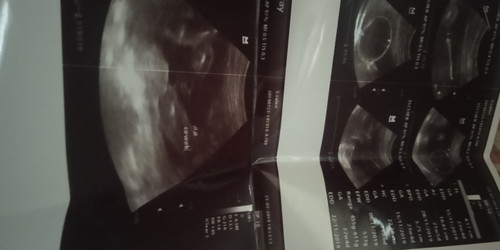

hasil usg

Bund saya mau tanya ini hasil USG saya ko di situ gak ada frekuensi detak jantung bayi yah tolong infonya

Gak ada bun . Dokternya ngga printout kali ya. Kemaren aku pernah gak di print terus kontrol selanjutnya aku nanyak. Terus di printoutin